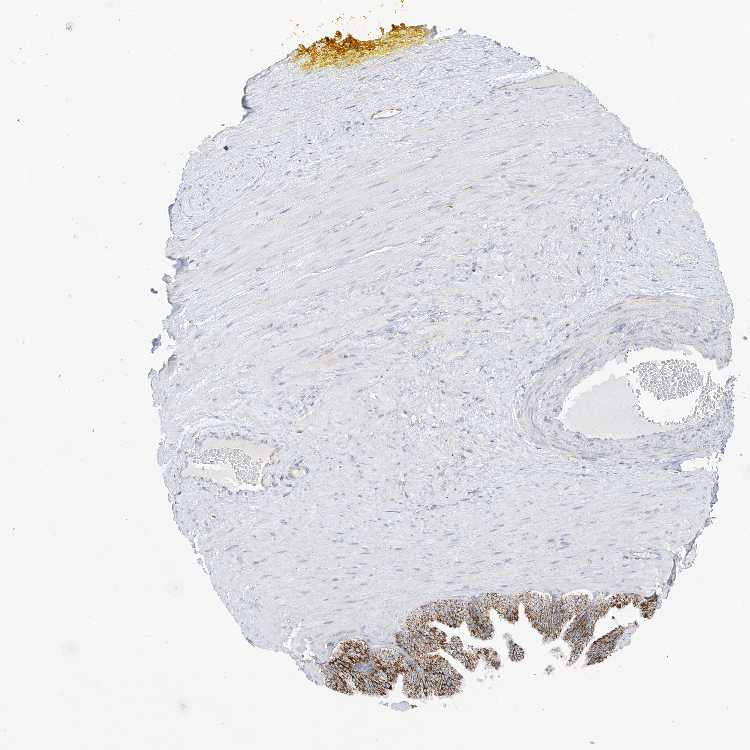

ADIPOSE TISSUE - Antibody stainingi

Antibody staining in the annotated cell types in the current human tissue is reported as not detected, low, medium, or high, based on conventional immunohistochemistry profiling in selected tissues. This score is based on the combination of the staining intensity and fraction of stained cells.

Each image is clickable and will lead to virtual microscopy that enables deeper exploration of all samples and also displays staining intensity scores, fraction scores and subcellular localization as well as patient and tissue information for each sample.

Antibody HPA029497Antibody HPA030034

Adipocytes LowLow